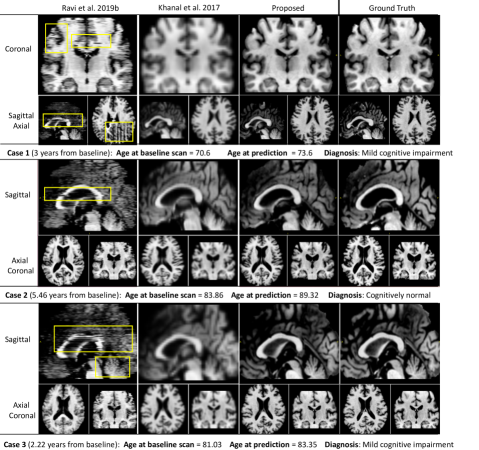

Refer to caption

Figure 5: Qualitative comparison study: Synthetic MRI, generated starting from the baseline scan, for three representative test cases (rows) across different MRI simulator models (columns).

5.1 Qualitative Comparison Study

Here we compare our framework to the two state-of-the-art solutions available for MRI synthesis: i) the baseline DANI-Net obtained by independent training (and stacking) of 2D slice models [38]; and ii) the biomechanical approach proposed in [20], which required down-sampling of the MRI resolution (by a factor of 2) for computationally feasible training times, followed by re-scaling to the original resolution using bilinear interpolation.

Figure 5 shows that our approach provides the best results: fewer artefacts and superior resolution (less smoothing). Notably, images generated by [20] show excessive smoothing, whereas images generated by [38] contain notable artefacts.